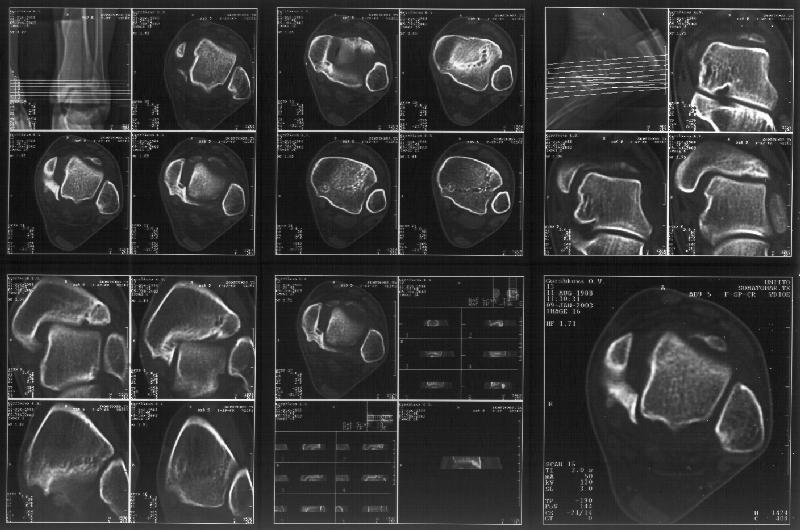

Re: Последствия травмы голеностопного сустава

BB> and what about bilateral comparative axial CT's to better define the

BB> ankle mortise pathoanatomy?

I attach CT of the affected ankle.